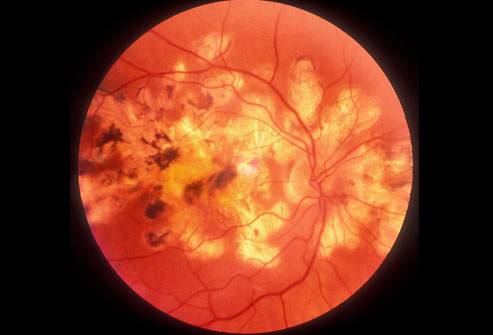

二型糖尿病

三分之一的糖尿病患者甚至不知道自己患了糖尿病。糖尿病会引起心脏病、中风、肾病、因视网膜血管受损导致失明(如图所示)和其他严重问题。你可以通过饮食、运动、减肥、和药物治疗来控制糖尿病,特别是在你发现得及时的情况下。2型糖尿病是常见的疾病。1型糖尿病的患者通常是儿童和年轻人。

糖尿病筛查

在进行血糖检查前你需要空腹8小时。血糖水平为6.1- 7.0mmol/L可能表明糖尿病前期;7.0mmol/L或更高意味着糖尿病。其他测试包括糖化血红蛋白测试和口服葡萄糖耐量试验。如果你很健康,且患糖尿病的风险属于正常水平,你应该从45岁起每三年接受一次筛查。如果你患病风险高,比如有糖尿病家族史,与医生沟通,看看你是否需要提前接受更频繁的筛查。